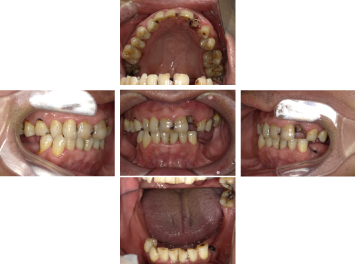

30代 女性 奥歯 インプラント

| 年代・性別 | 30代・女性 |

| 治療回数 | 10回(術前治療・検査除く) |

| 治療期間 | 約1年 |

| 料金 | ¥410,300(税込)※別途検査料 |

失った歯を補うために、インプラント治療は優れた治療方法です。 しかし、全ての人にインプラント治療が優れている治療ではありません。 |

| 副作用 | 術後に腫れ・痛みが出る可能性がある。 |